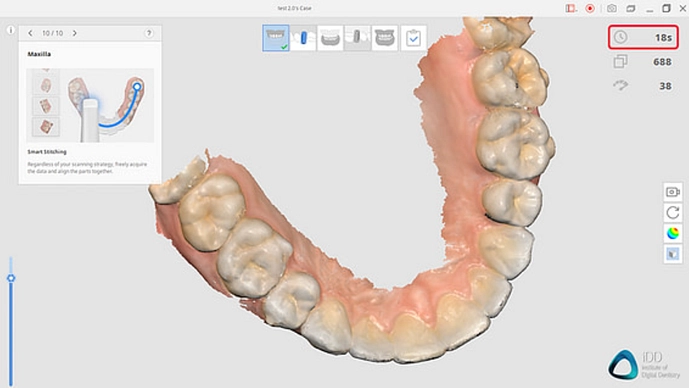

اسکنر سه بعدی در دندانپزشکی

یکی از فناوریهای پیشرفته در دندانپزشکی دیجیتال است که امکان ثبت دقیق شکل و ساختار دندانها و فک را فراهم میکند. اسکنر سه بعدی، جایگزین قالبگیری های سنتی و زمانبر شده و دقت درمان ها را به میزان قابل توجهی افزایش میدهد.

کاربردهای اسکنر سه بعدی در دندانپزشکی:

1. طراحی پروتز و ایمپلنت دقیق: اسکن سهبعدی باعث میشود پروتزها و ایمپلنتها با اندازه و شکل دقیق دندانهای هر بیمار ساخته شوند.

2. برنامهریزی درمان شخصیسازی شده: با تصاویر دیجیتال سهبعدی، دندانپزشک میتواند مسیر درمان و محل دقیق کاشت ایمپلنت را با دقت بالا برنامهریزی کند.

3. کاهش خطا و زمان درمان: اسکن دیجیتال، نیاز به جلسات مکرر قالبگیری را حذف میکند و سرعت درمان را افزایش میدهد.

4. ارتباط بهتر با لابراتوار دندانپزشکی: فایلهای دیجیتال اسکن بهراحتی برای ساخت پروتزها یا اجزای ایمپلنت به لابراتوار ارسال میشوند.